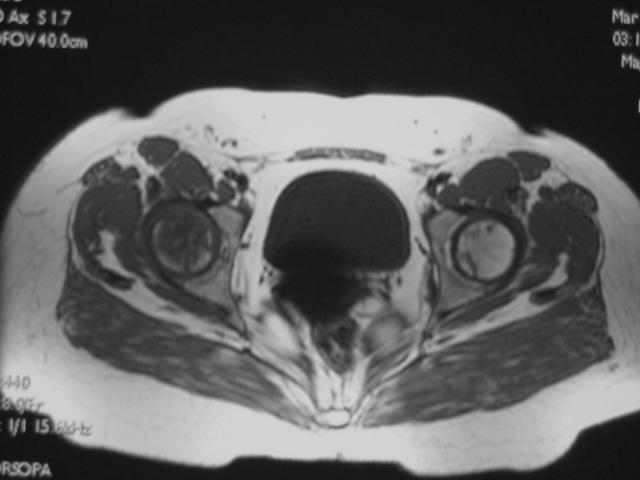

MRI诊断

MRI扫描技术

患者取仰卧位,扫描范围自髋臼上3cm至股骨粗隆下。

层厚5mm,层间距1mm连续扫描。

选择自旋回波SE序列T1WI、T2WI及STIR冠状面扫描,横轴位T1W扫描。